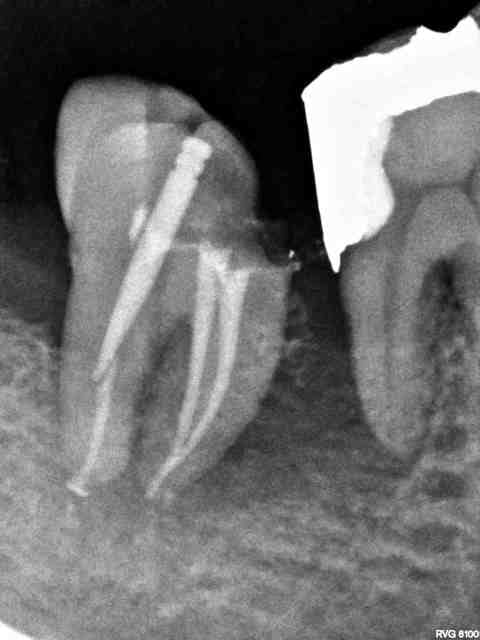

Risque de complication augmenté chez les patients fumeurs stressés mauvaise hygiène. Admirez la disparition du septum de ce patient fumant 40 cig/j, hyperstressé et à l'hygiène dégueulasse...

en même temps si tu reprends ta rétro initiale atteinte de furcation sur les deux molaires et je suis surpris de voir que personne ne t'ai encore dit que la digue aussi avait disparu à l'essayage des cones mais dans ce cas précis et vu le contexte tout ça ne va pas tenir longtemps pas de surprise...

Y a pas une nécrose de 46?

Et le bénéfice du doute les amis!! Bagheerra a peut être utilisé un crampon plastique, comme l'insti-dam par exemple, c'est radio clair je crois, et l'endo semble très bien obturée.

Sinon +1 pour la nécrose de 46, avec de grande chance d'être à l'origine de la perte osseuse.

La reconstitution pré-endodontique en mésial est également radioclaire.

Je crois que bagherra émet l'hypothèse que la lésion osseuse interdentaire, apparue entre les deux séances, soit due à une intraligamentaire. (bagherra?)

Effectivement, il n'y a que 1 mois entre les deux radios. La 46 est pour l'instant bien vivante. Il y a eu une gingivite nécrotique après dans les jours qui ont suivi l'anesthésie intraligamentaire.